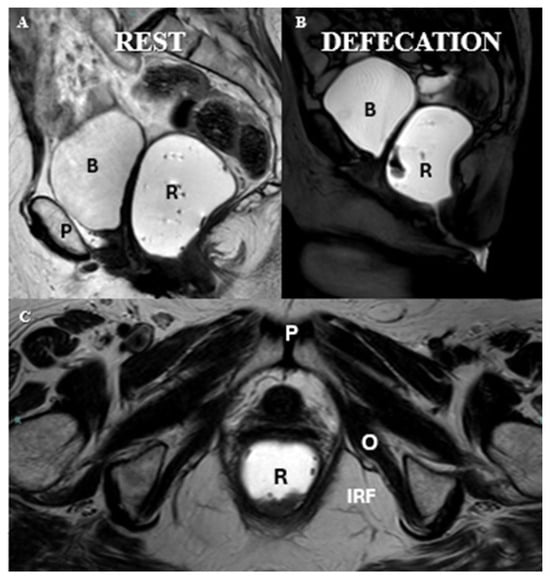

- High-resolution T2-weighted images in three orthogonal planes: axial, sagittal, and coronal.

- Optional dynamic sequences in axial and coronal planes during straining may be considered to further evaluate complex pelvic floor dysfunctions.

| Axial | T2 smFOV | Resting | Rectum through the gluteal folds |

| Coronal | T2 smFOV | Resting | Sacrum through pubic symphysis |

| Sagittal | T2 oblique | Resting | Slices through anal canal; rectum distended with ultrasound gel. |